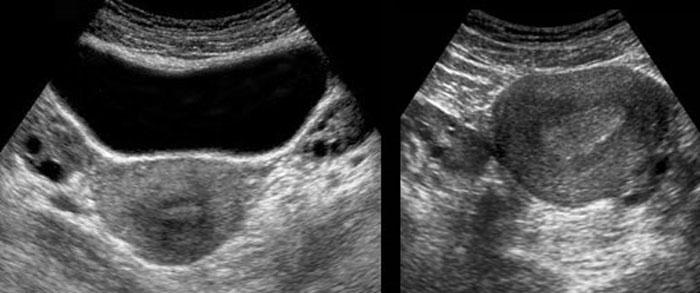

Dominant follicle

Ở phụ nữ trong độ tuổi sinh sản, buồng trứng bình thường ở trạng thái không hoạt động cho thấy mức độ mạch máu hóa vừa phải (hình bên trái).

Trong giai đoạn tiền rụng trứng, nang trội

có thể được nhận biết qua hình ảnh “vòng lửa” (hình bên phải).

Luteal body

Sau khi rụng trứng, nang trứng trội trở nên nhỏ hơn

(trái) và trong trường hợp không có thai, chuyển thành thể vàng có nếp nhăn (phải).